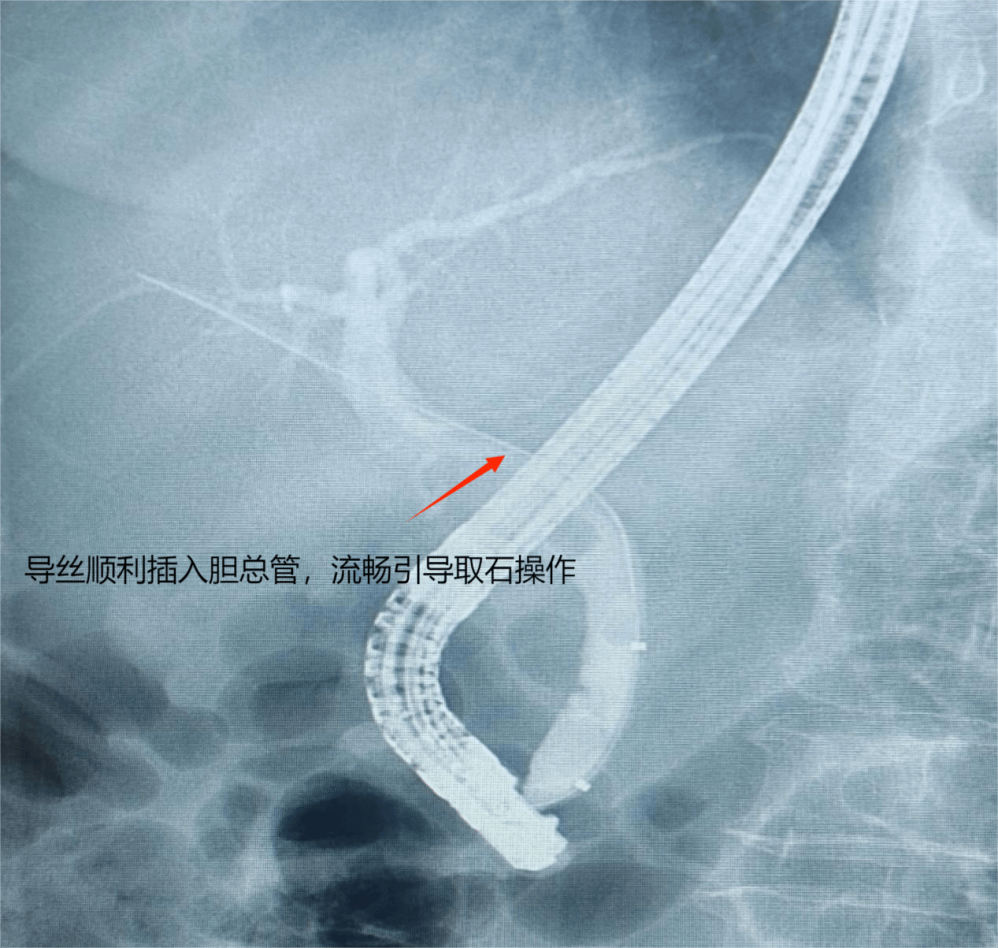

术中,叶军锋教授率先通过ERCP技术,简洁、高效、精准定位胆总管末端结石,在数字剪影X光引导下完成碎石、取石操作,成功疏通胆道;随后,刁守志教授团队接力开展腹腔镜胆囊切除术,在腹部仅开3个微小切口,便顺利切除病变胆囊。整个手术过程中,肝胆胰外科/疝外科与手术室团队密切配合,麻醉科实时监测生命体征,器械护士精准传递器械,每一个环节无缝衔接、高效协同。前后历经约两个小时,手术圆满完成,真正实现了“微创、精准、安全”的救治目标。